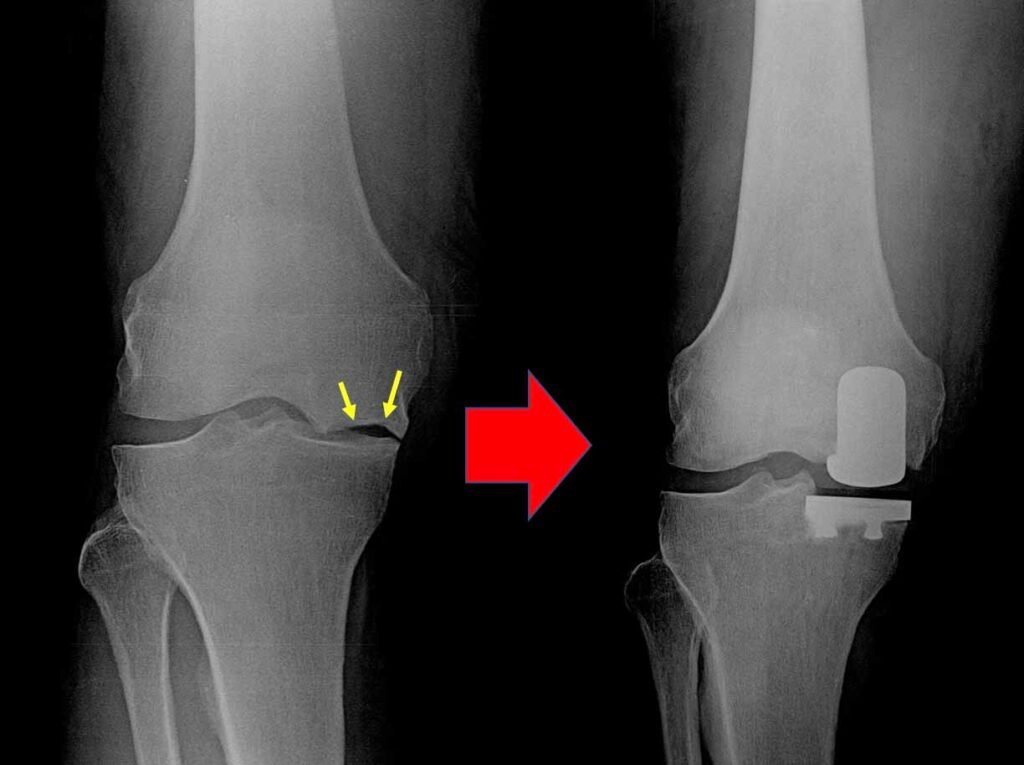

Knee Surgery GET IN TOUCH Knee Arthritis Meniscal Tears ACL Tears Knee Instability The Painful Or Failing Knee Replacement Radio Frequency Ablation Learn MOre Knee Arthroscopy Learn MOre ACL Reconstruction Learn MOre Partial Knee Replacement Learn MOre Total Knee Replacement Learn MOre PSI | KA | TOTAL KEE REPLACEMENT Learn MOre ROBOTIC-ASSISTED TKA Learn MOre REVISION KNEE REPLACEMENT Learn MOre KNEE CONDITIONS Learn MOre OUR SERVICES If joint pain or injury is affecting your daily life, Dr Paterson is here to support your recovery with individualised, evidence-based care. Radio Frequency Abolation (Knee) Learn MOre Knee Arthroscopy Learn MOre Anterior Cruciate Ligament (ACL) Reconstruction Learn MOre Partial Knee Replacement Learn MOre Total Knee Replacement Main Menu LEARN MORE Total Knee Replacement Surgery PATIENT SPECIFIC, KINEMATICALLY ALIGNED TOTAL KNEE REPLACEMENT ROBOTIC-ASSISTED TOTAL KNEE REPLACEMENT REVISION KNEE REPLACEMENT SURGERY LEARN MORE TOTAL KNEE REPLACEMENT PATIENT SPECIFIC (PSI), KINEMATICALLY ALIGNED TOTAL KNEE REPLACEMENT ROBOTIC-ASSISTED TOTAL KNEE REPLACEMENT REVISION KNEE REPLACEMENT SURGERY